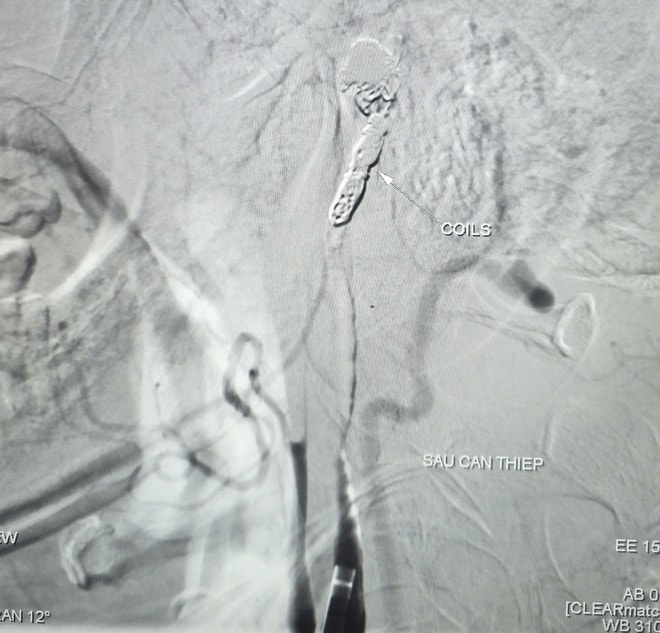

Hình ảnh thoát mạch trước và sau can thiệp. Ảnh: BVCC.

Kết quả chụp mạch ghi nhận ổ giả phình động mạch cảnh trong phải đoạn cổ, dưới nền sọ, kích thước khoảng 4,2 x 4,8 mm, cổ túi phình rộng và đang chảy máu. Ê kíp can thiệp đã sử dụng bóng để kiểm soát dòng chảy, sau đó đưa vi ống thông đến vị trí tổn thương và thả 9 vòng xoắn kim loại (coils) nhằm gây tắc hoàn toàn túi phình và đoạn động mạch cảnh trong phải, qua đó kiểm soát nguồn chảy máu.

Chụp kiểm tra sau can thiệp cho thấy não vẫn được tưới máu nhờ hệ tuần hoàn bàng hệ từ động mạch cảnh trong bên trái qua động mạch thông trước. Toàn bộ thủ thuật được hoàn tất trong khoảng 90 phút. Sau can thiệp, bệnh nhân được theo dõi tích cực. Đến ngày 6/3, người bệnh tỉnh táo, tiếp xúc tốt, niêm mạc hồng, không ghi nhận yếu liệt tay chân, sức khỏe phục hồi ổn định.